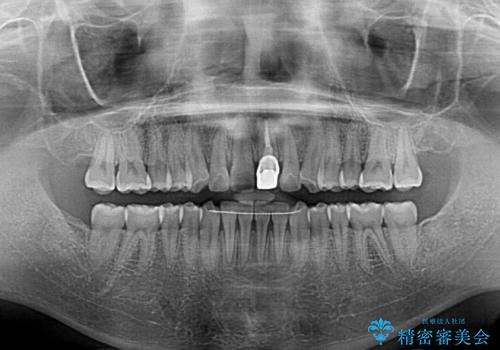

- 前歯の歯並びと不自然な色をした前歯のクラウンを気にして来院された患者様です。

上下前歯の歯列不正はインビザラインにより歯列を整え、その後に、前歯をオーダーメイドタイプのオールセラミッククラウンにて補綴治療することとしました。

初診時には、歯並びを整えることのみを検討されていましたが、歯列が整うにつれて不自然な色合いが気になるようになり、矯正治療を行ってから補綴治療をする計画を受け入れてくださいました。